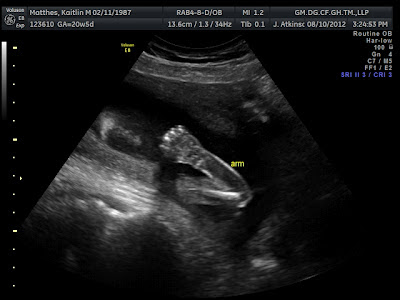

| These last 2 are from the US on 8/10/12. Just more proof of the parts! :) |

Because you can see her legs on this one, you can better tell what angle you are looking at here.

The arrow is pointing to the three white lines (which are the labia) and you can clearly see

that there is nothing else between those legs :) |